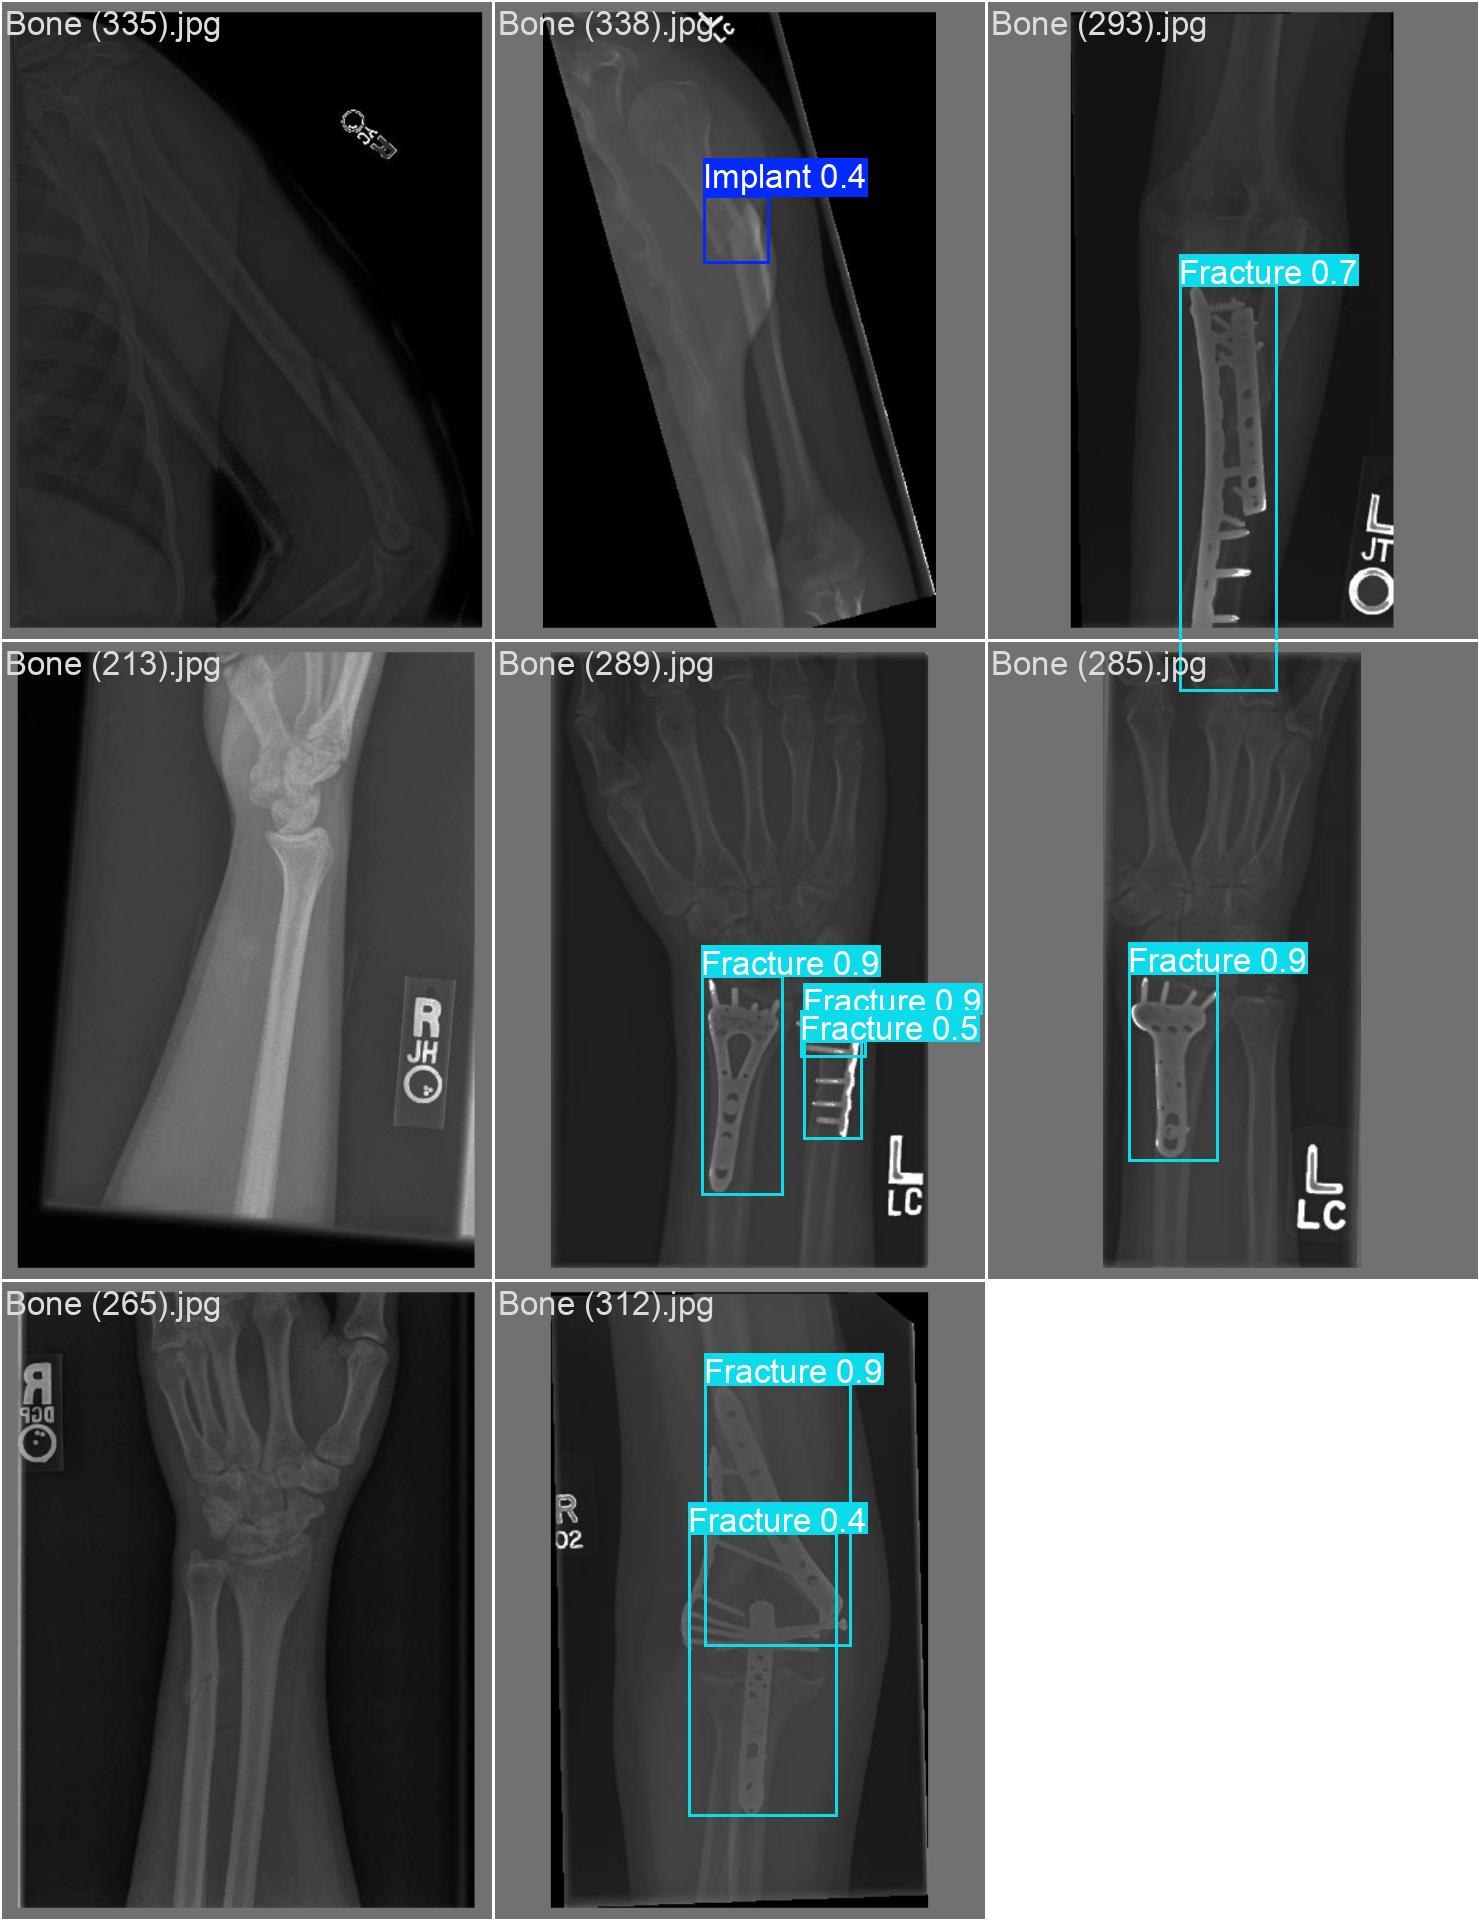

20251204_04 train2

| model | yolov8s.pt | |

| imgsz | 800 | |

| batch | 16 | |

| epochs | 60 | 다시 60으로 내려왔다. 60이 최선인 것 같다 |

| optimizer | auto |

20251204_04 predict2

class 반대로 되어있는 파일 수정 안 했다

| conf | 0.3 | |

| iou | 0.5 | 이것만 줄여보기 |

iou는 별로 효과가 없는 듯